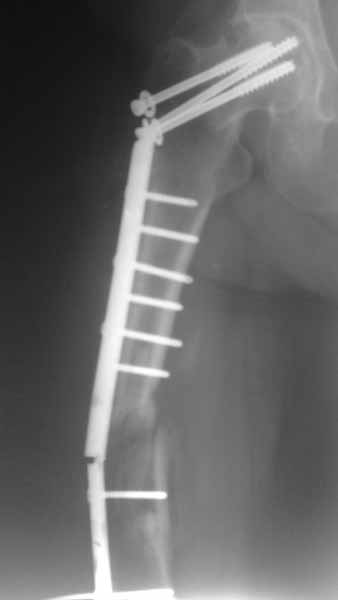

Псевдоартроз бедра

Уважаемые коллеги. Помогите определить тактику лечения. Больной 51 год.

Оперирована 12 месяцев назад в связи с медиальным переломом шейки бедренной кости и оскольчатым переломом диафиза бедренной кости. На то время в Украине не было систем БИОС, позволяющих фиксировать одновременно оба перелома, поэтому выполнена фиксация тем, чем могли. Около 1 мес назад больная начала передвигаться с тростью. Что в данном случае лучше сделать?